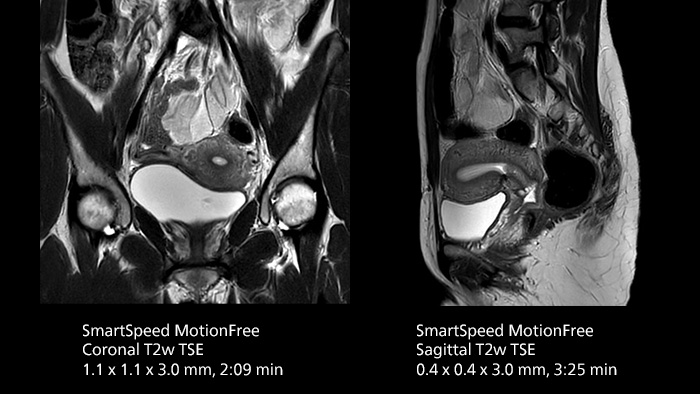

After using Philips SENSE, Mermaid Beach had adopted Compressed SENSE that offers a k-space sampling approach to speed scans while preserving details. “And now SmartSpeed enables denoising the sparse under-sampling in a new way that has allowed us to increase acceleration and bring image quality to a whole new level,” notes Kennedy, “It’s truly revolutionized our MRI work space, especially for difficult patients.”

Philips SmartSpeed has multiple approaches to denoising. Raw k-space data, coil sensitivity and coarse background information are all used and reconstructed with artificial intelligence (AI) to provide true resolution in shorter scan times1 with more sequences. Kennedy states, “I noticed that since the introduction of SmartSpeed, our day is a lot less stressed. When complicated exams need extra time, we just get on with them. And if we need to do something new or extra, we have the time for it and our workflow is still a lot more efficient.”

In addition to workflow benefits, Kennedy highlights the improvement in their diagnostic confidence. “The quality of output is so much higher than what we believed was possible, and it is very consistent across multiple patients. SmartSpeed made it feasible for us to include extra sequences in our exams and still maintain routine scanning times. This allows us to make a surprising number of diagnoses that we couldn’t have appreciated before with our previous protocol. We’ve gotten an extremely positive response from our referrers.”

The broad applicability of SmartSpeed allowed the imaging center to use this technology across many scan types, including non-cartesian imaging as used for motion correction in uncooperative patients or challenging anatomies.

“We use SmartSpeed frequently on difficult areas such as the abdomen and chest where it is common to see respiratory motion and other bowel motion,” says Kennedy. In MSK scans they use SmartSpeed not only for speeding up their exams, but also to reduce slice thickness and improve resolution “We may be increasing the number of slices, but we’re still doing this in less time than we were previously.”